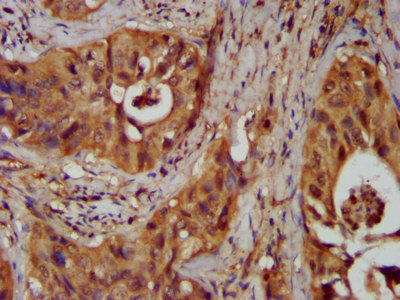

IHC image of PACO57892 diluted at 1:300 and staining in paraffin-embedded human prostate cancer performed on a Leica BondTM system. After dewaxing and hydration, antigen retrieval was mediated by high pressure in a citrate buffer (pH 6.0). Section was blocked with 10% normal goat serum 30min at RT. Then primary antibody (1% BSA) was incubated at 4°C overnight. The primary is detected by a biotinylated secondary antibody and visualized using an HRP conjugated SP system.

IHC image of PACO57892 diluted at 1:300 and staining in paraffin-embedded human cervical cancer performed on a Leica BondTM system. After dewaxing and hydration, antigen retrieval was mediated by high pressure in a citrate buffer (pH 6.0). Section was blocked with 10% normal goat serum 30min at RT. Then primary antibody (1% BSA) was incubated at 4°C overnight. The primary is detected by a biotinylated secondary antibody and visualized using an HRP conjugated SP system.